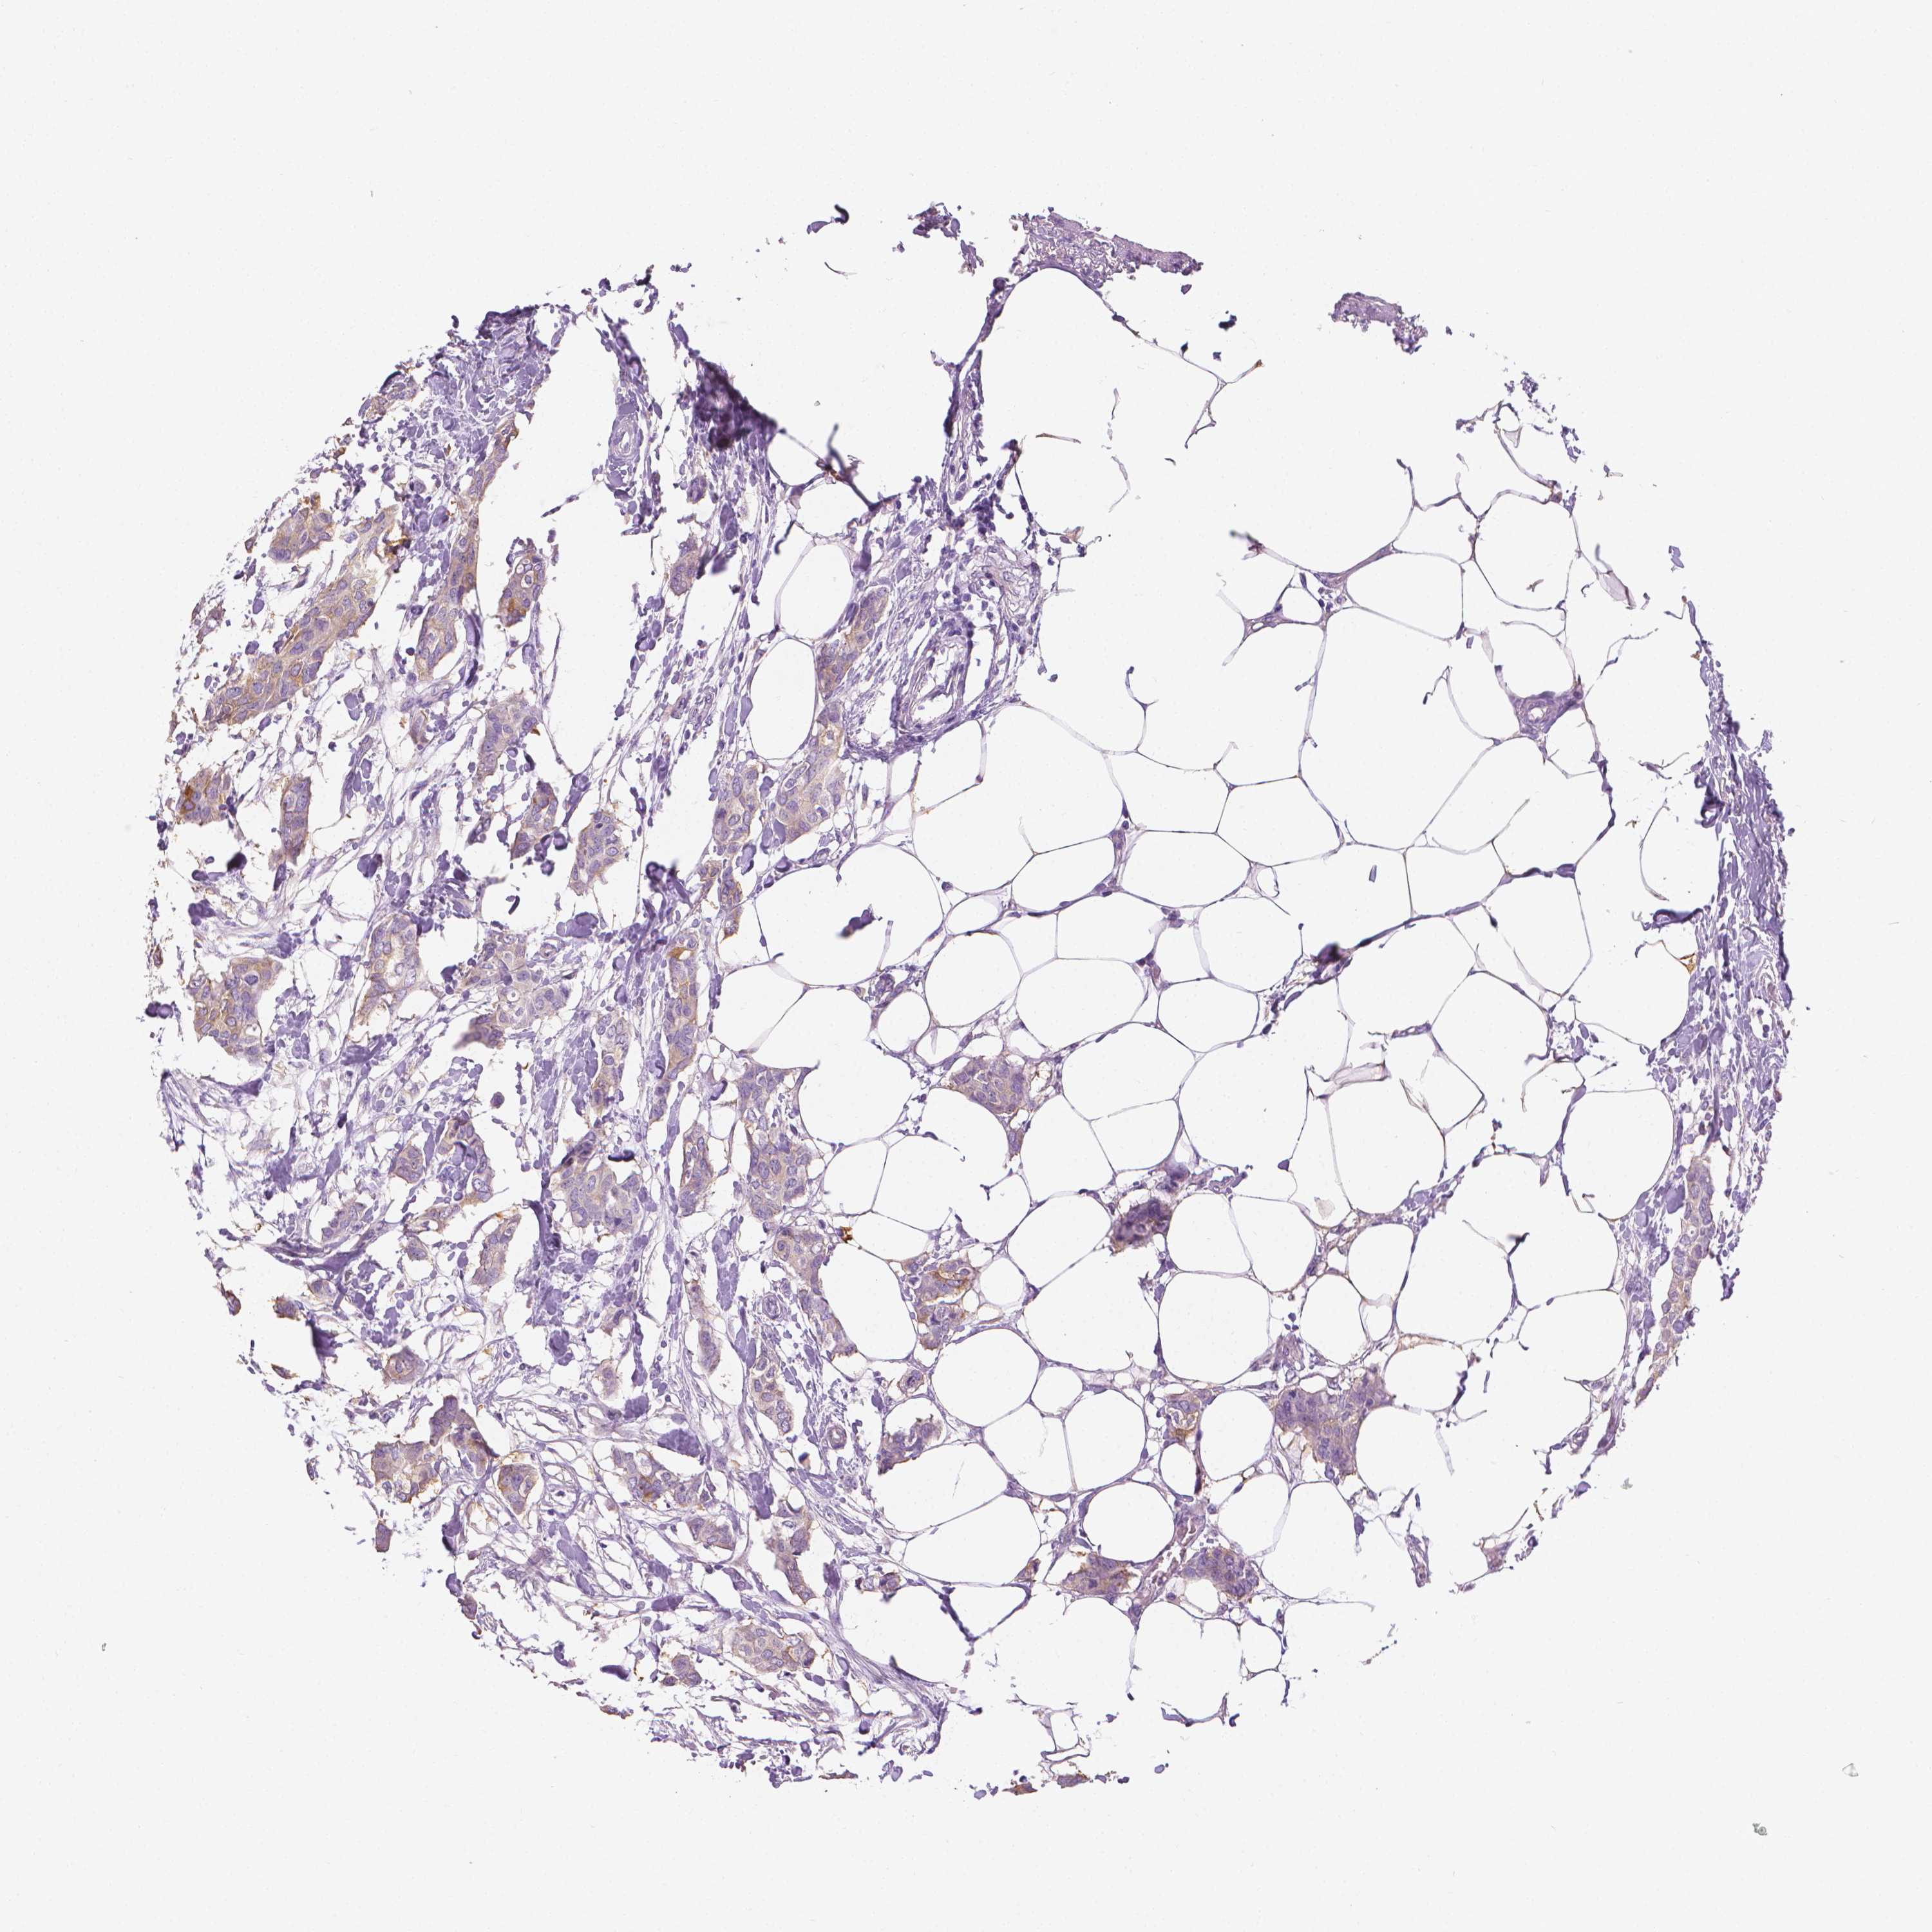

CANCER BREAST CANCER Show tissue menu

BRCA TCGA BRCA VALIDATION PROTEIN EXPRESSION

ANTIBODIES

AND

VALIDATION